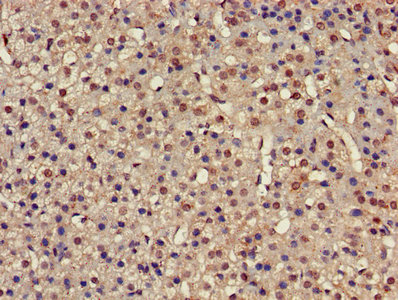

IHC image of CSB-PA018894LA01HU diluted at 1:500 and staining in paraffin-embedded human glioma performed on a Leica BondTM system. After dewaxing and hydration, antigen retrieval was mediated by high pressure in a citrate buffer (pH 6.0). Section was blocked with 10% normal goat serum 30min at RT. Then primary antibody (1% BSA) was incubated at 4°C overnight. The primary is detected by a biotinylated secondary antibody and visualized using an HRP conjugated SP system.